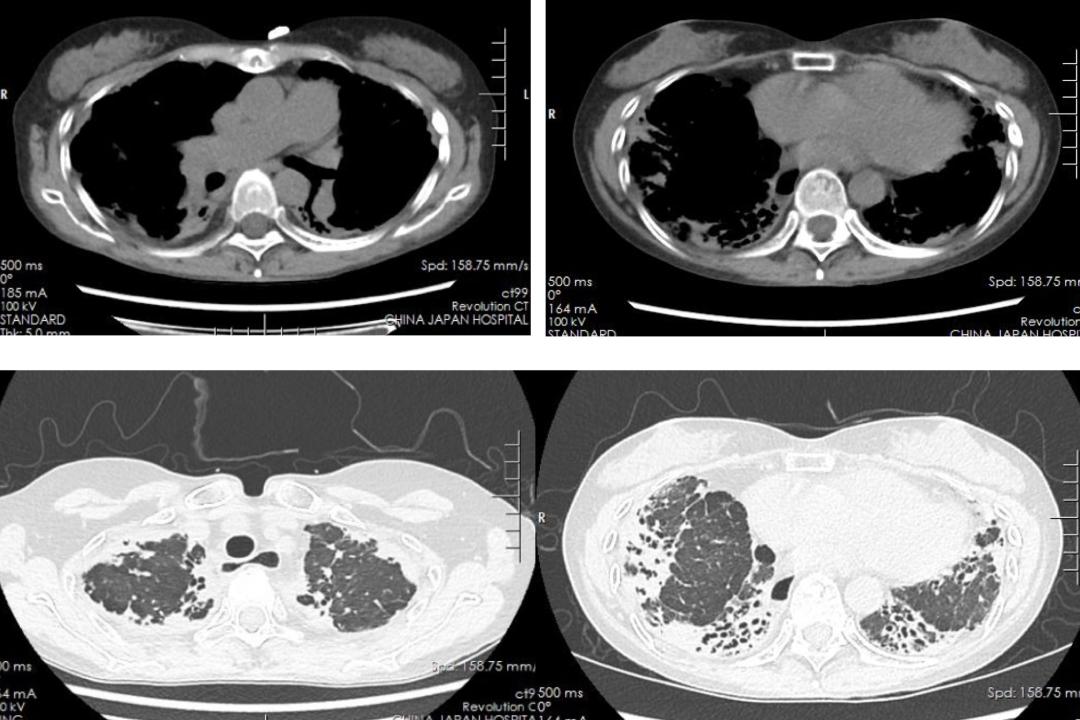

d.影像检查:

胸部HRCT:双肺小叶间隔增厚,胸膜下可见蜂窝样改变;肺动脉增宽,右心扩大。提示患者存在间质性肺病与右心衰的器质性病理改变。